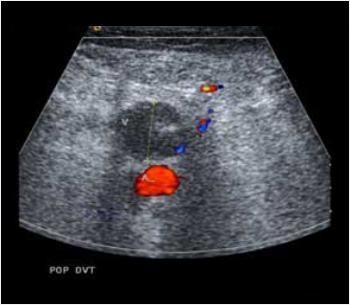

Venöz Doppler Ultrason

Venöz Doppler Ultrason, ultrasona ek olarak, kan akış hızını ve damarlardaki kan akışının yönünü değerlendirmek için Doppler adlı bir modüle sahiptir.

Renkli Doppler modülüyle, akış yönlerine bağlı olarak akışlar renkli, kırmızı veya mavi olarak görünür.

Doppler, venöz ağın (toplardamar sistemi) araştırılmasına izin veren temel incelemedir. Herhangi bir varis tedavisinden önce yapılması gereklidir , ancak bazen venöz tromboz veya " flebit " (damarların bir pıhtı ile tıkanması) şüphesi durumunda acil olarak da uygulanır.

Doppler incelemesi, derin veya yüzeysel venöz trombozu (“flebit”),yani damarların pıhtı ile tıkanmasını tespit etmeyi mümkün kılar. Venöz pıhtılar, yer değiştirirse pulmoner arterleri tıkayabilir: en yaygın tezahürü göğüs ağrısı veya ani nefes darlığı olan pulmoner embolizmdir. Doppler ultrason, venöz trombozun yerini ve kapsamını inceler.